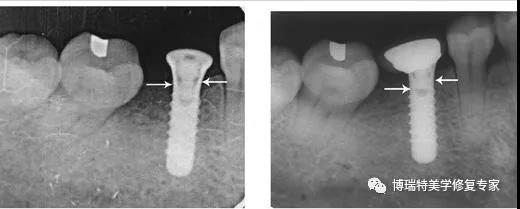

2.种植体周围骨吸收

有学者认为初始骨吸收0.5 mm,然后每年生理性吸收100 μm一般认为种植体周围骨吸收在修复后一年内超过1 mm,以后以每年吸收超过0.2 mm时即可认为有病理性骨吸收存在。引起种植体周围骨吸收的因素很多,包括吸烟、过度负荷、口腔卫生不良等。